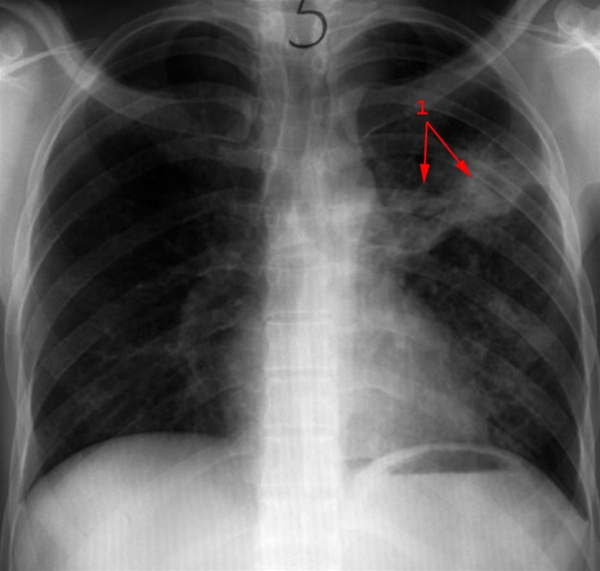

Lunger, røntgen, primær tuberkulose, før behandling

Primær tuberkulose - billede 1

Udbredte fortætninger i venstre lunge (1). Før behandling.

Se billede 2: Primær tuberkulose, behandlet, røntgen